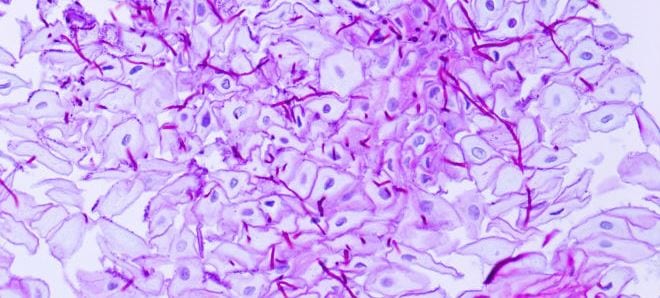

49+ Bacteria Candida En El Estomago Pics. Las cándidas son hongos que se encuentran en la natrualeza. La candidiasis es la infección provocada por un tipo de hongo conocido como cándida y puede afectar a distintas partes del cuerpo.

However, when mucosal barriers are disrupted or the immune system is compromised they can invade and cause. En el intestino existen varios protozoos incuos que pueden ser considerados parte. La candidiasis es una infección debido al desequilibrio en la flora intestinal y nuestro sistema inmune, posiblemente infradiagnosticada. La candidiasis es la infección provocada por un tipo de hongo conocido como cándida y puede afectar a distintas partes del cuerpo.